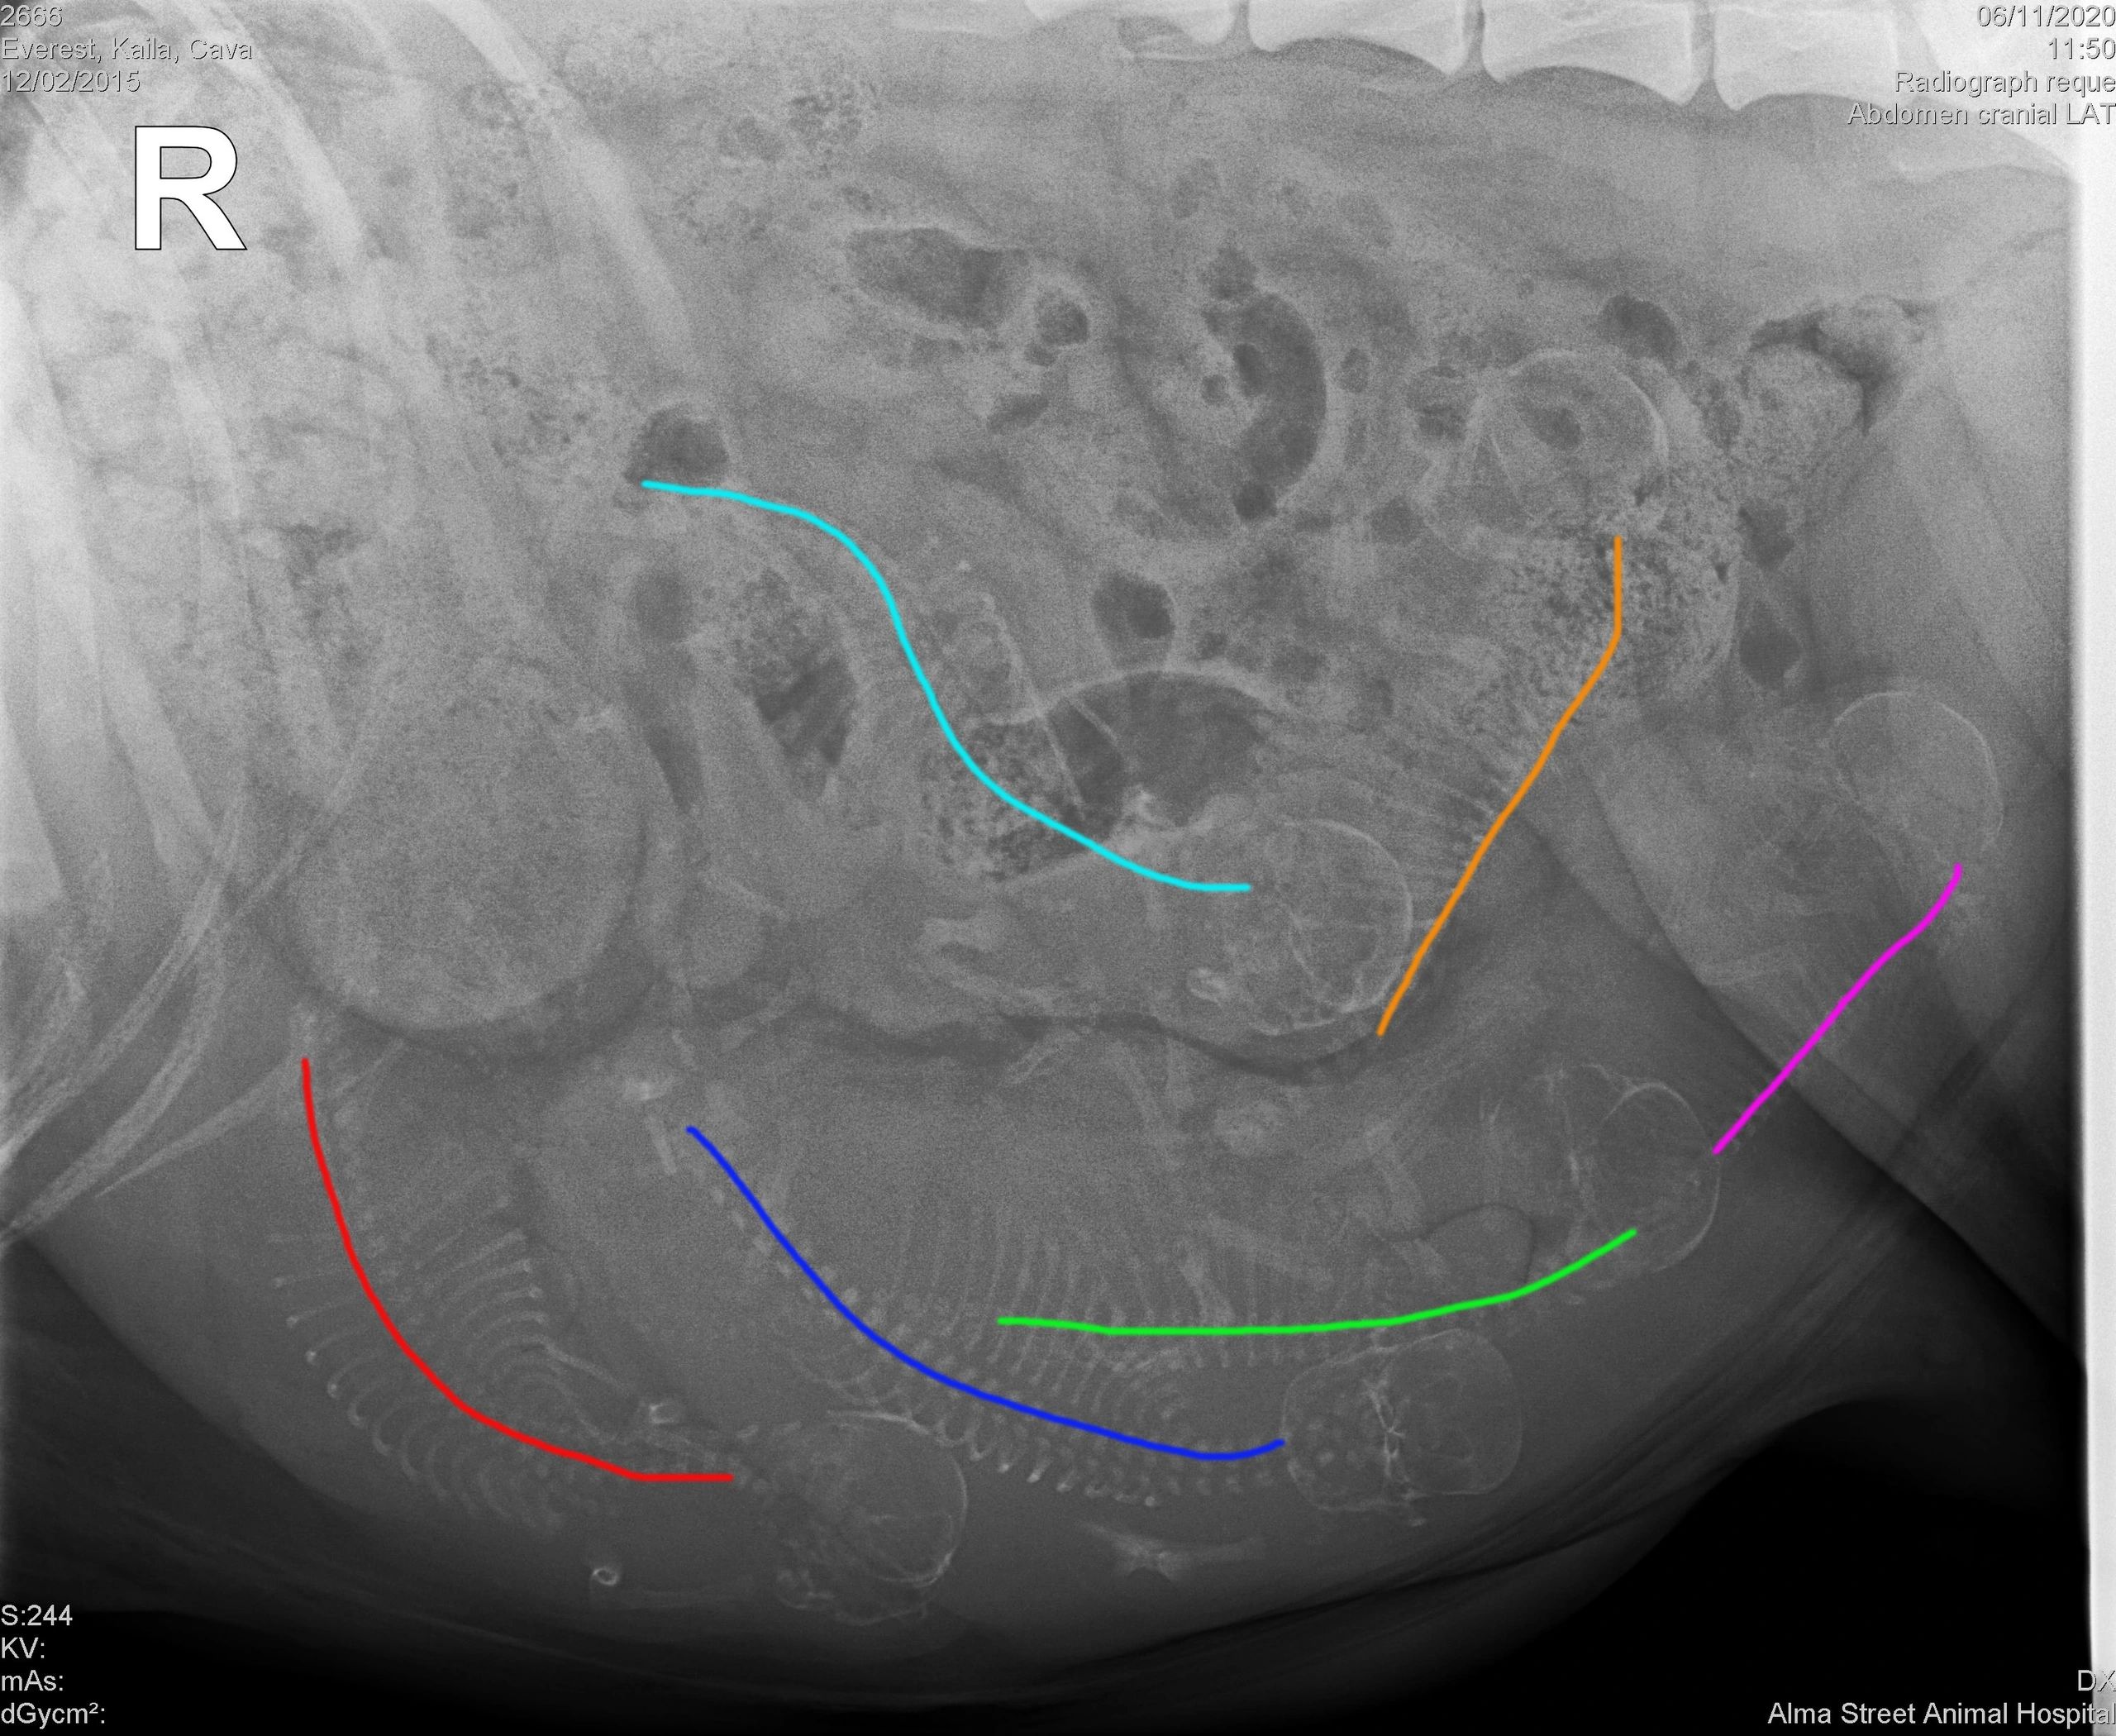

AM CH Top Shelf's Drunk on a Plane "Bentley" and AM/CAN CH Top Shelf's Last Call at Sunvalley - "Cava"

Cava welcomed five boys and one girl on June 18, 2020.